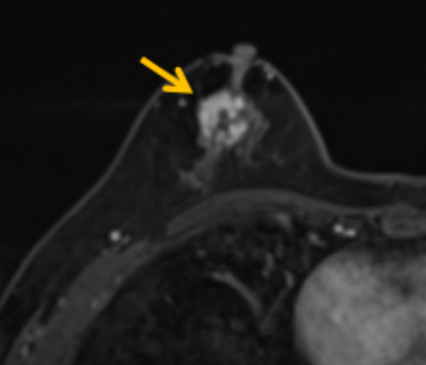

陳寶瑩評估圖像后發(fā)現(xiàn)病變?yōu)閮H僅在磁共振增強時顯示,為非腫塊樣病變,比較散,必須取得足夠多的組織才能確保病理檢查的準(zhǔn)確性,常用的核芯針活檢獲取的組織較少,因此最終確定了磁共振引導(dǎo)下行真空輔助抽吸旋切活檢。取得患者及家屬認(rèn)可后,陳寶瑩帶領(lǐng)團(tuán)隊開始進(jìn)行術(shù)前準(zhǔn)備。

針對患者乳房小固定難度大這一問題,陳寶瑩通過巧妙體位和固定器的調(diào)整,順利固定好乳房。經(jīng)過磁共振多模態(tài)掃描,陳寶瑩找出病變活性成分相對集中區(qū)域,精準(zhǔn)確定穿刺路徑,置入引導(dǎo)針、旋切針,到位后多角度旋切取出足量組織,拔除旋切針后即時行磁共振掃描,精準(zhǔn)取得組織且術(shù)區(qū)出血很少,遂加壓包扎,整個過程非常順利,旋切活檢后患者回家休息。兩天后隨訪,李女士沒有任何不適,五天后皮膚上幾毫米的小切口已經(jīng)愈合。最終病理結(jié)果證實為乳腺導(dǎo)管原位癌,為早期乳腺癌,為患者后續(xù)針對性治療奠定了基礎(chǔ)。